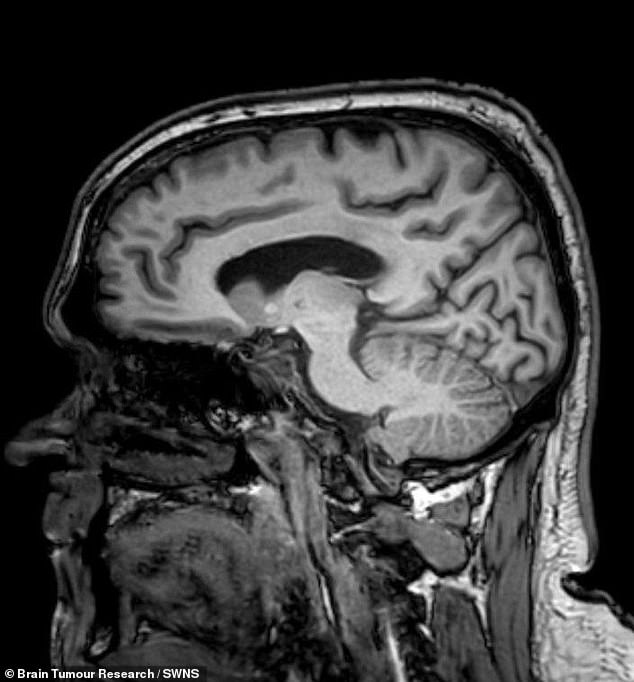

The story took a harrowing turn in 2022 when Mr. Brunt, driving to pick up furniture, suffered a sudden seizure that resulted in a collision and a blood-soaked aftermath. The incident, which left him hospitalized, was the moment his condition could no longer be ignored. CT scans at Chesterfield Royal Hospital revealed a glioblastoma, an aggressive, incurable brain cancer that had been growing silently for years. This aggressive tumor, which accounts for about 15% of all brain tumors in adults, is notorious for its rapid progression and resistance to treatment. Surgeons at Royal Hallamshire Hospital in Sheffield later removed the visible mass, but the prognosis initially gave Mr. Brunt only seven months to live.